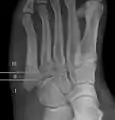

For several reasons, a Jones fracture may not unite. The diaphyseal bone (zone II), where the fracture occurs, is an area of potentially poor blood supply, existing in a watershed area between two blood supplies. This may compromise healing. In addition, there are various tendons, including the fibularis brevis and fibularis tertius, and two small muscles attached to the bone. These may pull the fracture apart and prevent healing.

Zones I and III have been associated with relatively guaranteed union and this union has taken place with only limited restriction of activity combined with early immobilization. On the other hand, zone II has been associated with either delayed or non-union and, consequently, it has been generally agreed that fractures in this area should be considered for some form of internal immobilization, such as internal screw fixation.

These zones can be identified anatomically and on x-ray adding to the clinical usefulness of this classification.[21] Surgical intervention is not, by itself, a guarantee of cure and has its own complication rate. Other reviews of the literature have concluded that conservative, non-operative, treatment is an acceptable option for the non-athlete.[22]

Anatomy of the fifth metatarsal.

3 zone description

2 zone description